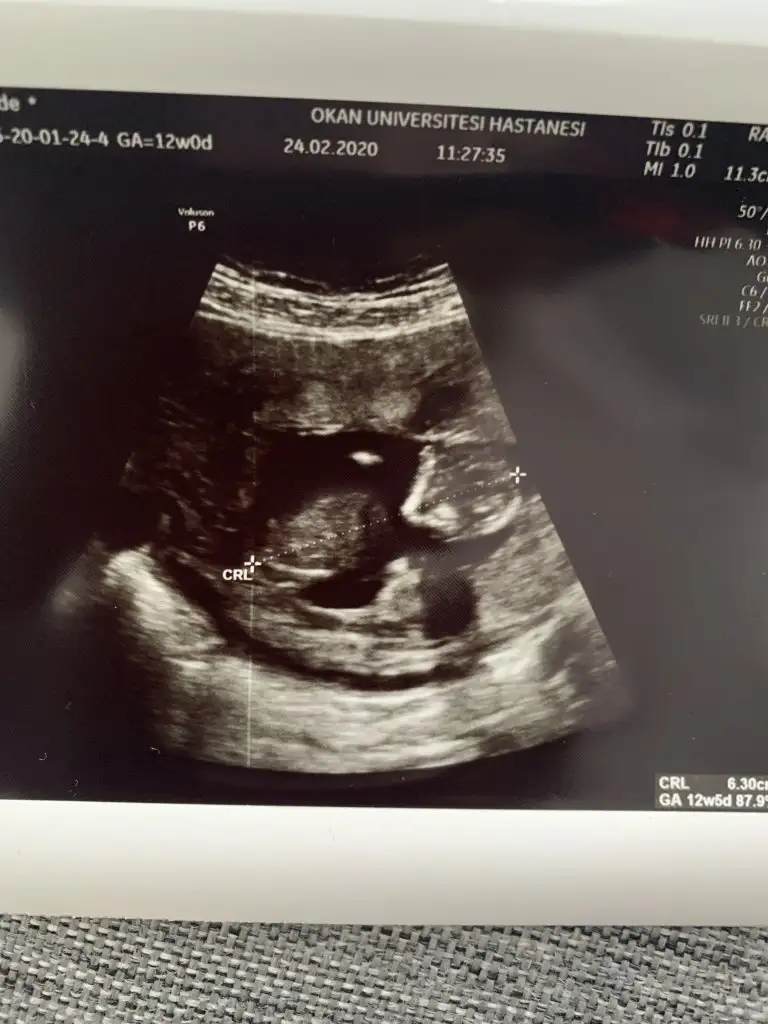

dr soylemeden siz gorun genital nub teorisi ( bebegin cinsiyeti)

Benimkinede bakar mısınız?

10+2yiz ama burda daha dr kontrolumüze var ben çıkıntı falan göremedim kızlar ya yardim edin 😅